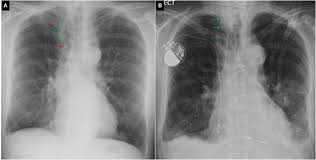

Loculated pleural fluid in a fissure can mimic a pulmonary mass and hence is sometimes referred to as a pseudomass or pseudotumor. Pleural effusion predominantly presents with breathlessness, but cough and pleuritic chest pain can be a feature. Blunting of the lateral costophrenic angle usually requires about 175 ml but may take as much as 500 ml. However, if the fluid has accumulated in this cavity, an opacity in this space is visible. Pet and mri scans provide even further detail and may be used to differentiate pleural thickening from malignant mesothelioma. Pocus demonstrated a large right sided loculated pleural effusion with associated septations and surrounding consolidation suggestive of a parapneumonic effusion. Pleural effusion with a missing breast suggesting resection for cancer : 1) to see if loculated or free fluid 2) to determine if enough volume to do a thoracocentesis (volume required is greater than 1cm) A pleural effusion is a collection of fluid in the space between your chest wall and lungs. Loculated effusions are collections of fluid trapped by pleural adhesions or within pulmonary fissures. 02, 2015 37,660 views prepared by medical student of nepal. Loculated pleural effusions can occur in isolation and, as in this case, be idiopathic. An ultrasound, chest computed tomogr.

Pleural effusion with nodes or mass or lytic bone lesions: Loculated effusions are defined as effusions that do not shift freely in the pleural space and occur in children with empyema when there are adhesions between the visceral and parietal pleura 5. Loculated pleural effusion causing pseudomass. Pleural effusion with apical infiltrates: The hilum is visible through the mass.

There is a wide differential for mediastinal masses. We present a unique case in which a patient presented to the ed in respiratory distress. Loculated pleural effusion causing pseudomass. We studied the value of transca … Chest radiographs are the most commonly used examination to assess for the presence of a pleural effusion;

Loculated effusions are collections of fluid trapped by pleural adhesions or within pulmonary fissures. Pleural effusion with a missing breast suggesting resection for cancer : Pocus demonstrated a large right sided loculated pleural effusion with associated septations and surrounding consolidation suggestive of a parapneumonic effusion. The excess accumulation of fluid can usually be seen on these images. Tried, tested, trusted and affordable for all qpcr needs. The hilum is visible through the mass. An ultrasound, chest computed tomogr. If the fluid cannot be drained, the lungs aren't able to expand and oxygenate the blood sufficiently. Chest radiographs are the most commonly used examination to assess for the presence of a pleural effusion; Pleural effusions are characterized on ct by attenuation values between those of water (0 hounsfield units hu) and soft tissue (approximately 100 hu), typically in the order of 10 to 20 hu. Dome shaped opacity projecting into the lung noted tracking along the cp angle and lateral chest wall suggestive of loculated pleural effusion, however the possibility of empyema can not be ruled out completely. Fibrotic scar tissue may form in the pleural cavity (called loculation), preventing effective drainage of the fluid. Treatment may fail if the catheter is not placed optimally within the loculation or if the fluid is hemorrhagic or fibrinous.

A lateral decubitus projection is most sensitive, able to identify even a small amount of fluid loculated pleural effusion. Pleural effusion predominantly presents with breathlessness, but cough and pleuritic chest pain can be a feature.